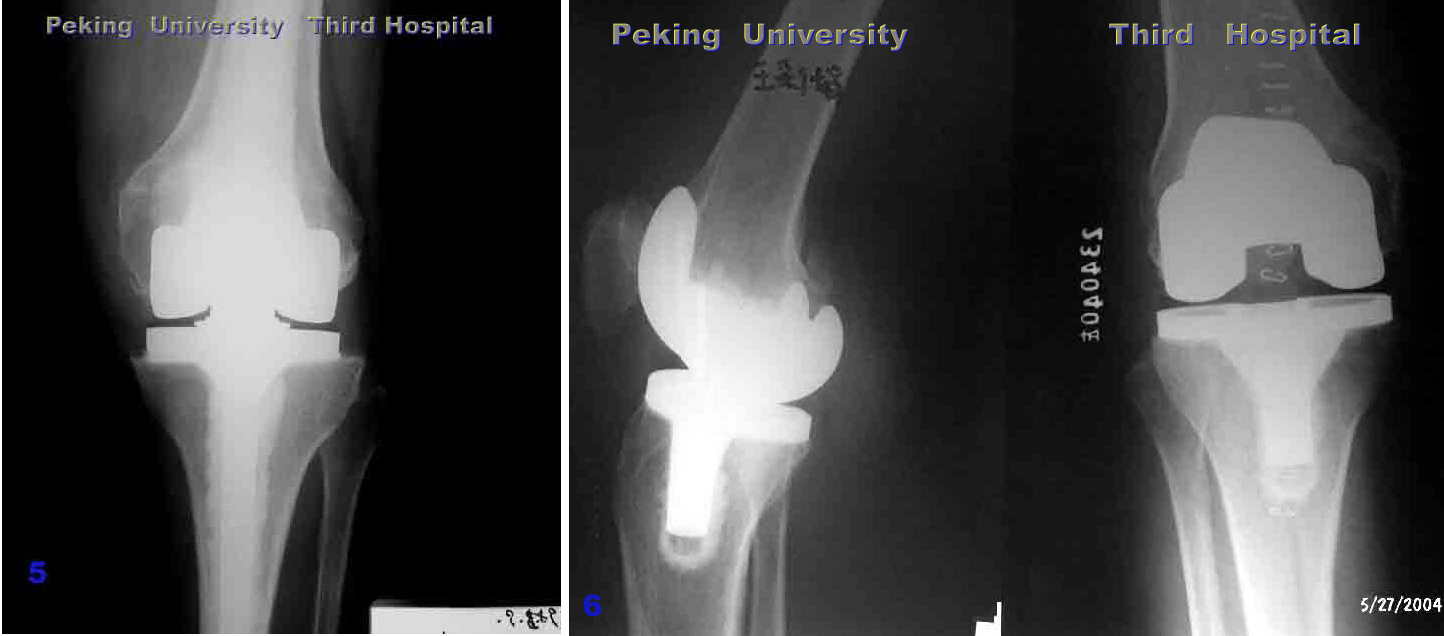

严重膝内翻,胫骨平台内侧植骨,软组织松解,术后内翻纠正

内 翻